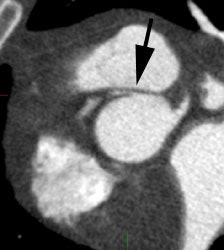

Anomalous RCA origin

from the left coronary sinus: The patient below underwent

coronary CT angiography to assess for coronary artery

disease. The patient was found to have an anomalous

RCA arising from the left sinus of valsalva. The

vessel can be seen to course between the pulmonary

trunk and aorta (black arrows) |